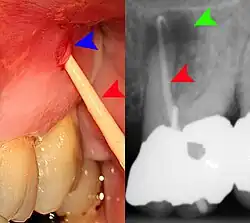

Plastic wedge to identify pain on biting from a fractured tooth Plastic wedge to identify pain on biting from a fractured tooth

Transillumination demonstrating fracture Transillumination demonstrating fracture

Decay (green) with apical abscess (blue) Decay (green) with apical abscess (blue)

Gutta-percha point indicating abscess origin Gutta-percha point indicating abscess origin